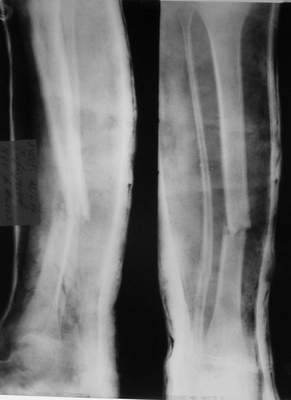

A>> Перелом костей н\3 правой голени со смещением.

AVM> Это от 13.10.04? А это близкие к первичным снимки?

Так как речь зашла непосредственно о травме, см этапные

снимки. Как все было

Первичные